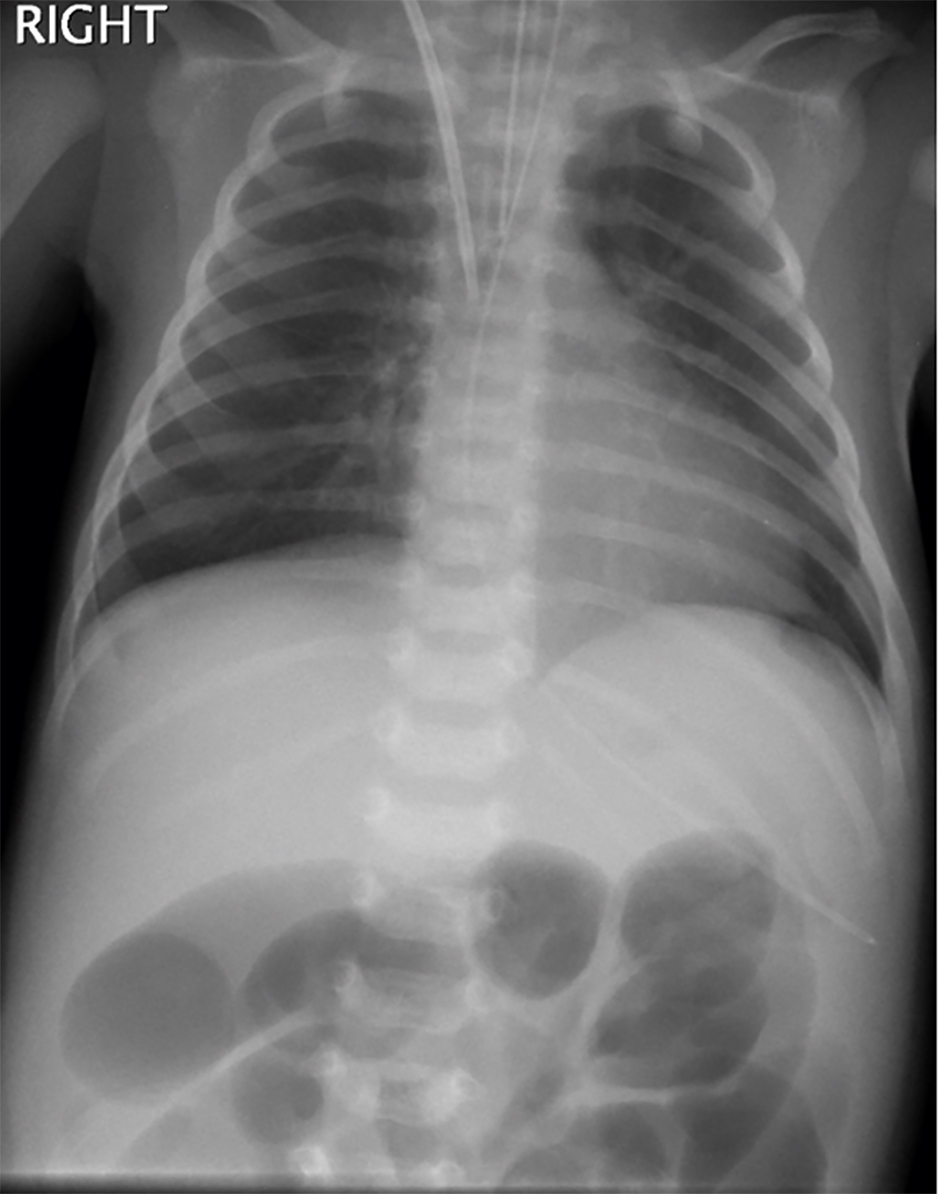

Chest radiograph showed clear lung fields (Fig. 1). Abdominal radiograph showed dilated bowel loops (Fig. 2). There were no signs of sepsis on chest radiograph and NEC on abdominal radiograph. As she continued to deteriorate, she was referred to and transferred to us on the third day of admission for small bowel obstruction with bowel ischemia.

![]() Click for large image | Figure 1. Chest radiograph showing dilated bowel loops in upper abdomen. |